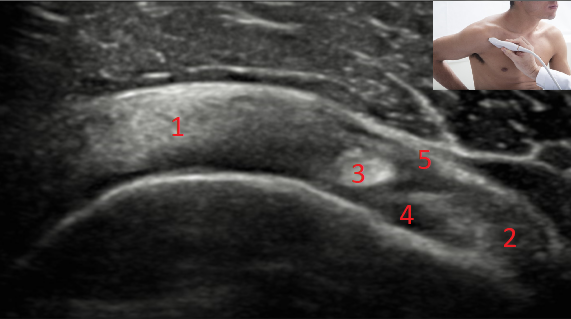

QUAIS AS ESTRUTURAS NUMERADAS NA FIGURA?

1 - TENDÃO DO SUPRAESPINHAL

2 - TENDÃO DO SUBESCAPULAR

3 - TENDÃO DA CABEÇA LONGA DO BÍCEPS (INTRARTICULAR)

4 - LIGAMENTO GLENO-ULMERAL

5 - LIGAMENTO CORACO-ULMERAL